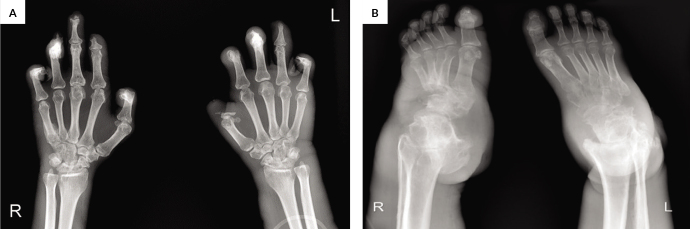

Occupational acro-osteolysis pertains to bone resorption of the distal phalanges of the hands and feet among workers with vinyl chloride exposure. We report the case of a Filipino man with osteolysis of the distal phalanges of the hands initially considered to have systemic sclerosis. The patient had gradual shortening of the fingers, thickening of the skin over the extremities, and hypopigmented patches over a span of more than 20 years. His lower extremities presented with non-pitting edema, skin thickening, and neuropathy, without shortening of the digits. Difficulty of ambulation was apparent due to the development of feet inversion. Radiographic findings of the hands and feet included resorption of distal phalanges, erosive and sclerotic changes, and narrowed joint spaces. Other conditions considered were Hansen's disease, skeletal tuberculosis, and diabetic neuropathic arthropathy, which were eventually ruled out. The final diagnosis was occupational acro-osteolysis secondary to vinyl chloride exposure. The patient underwent serial total contact casting of the bilateral lower extremities to relieve bipedal edema and to reposition the feet. This case emphasizes the significance of investigating a patient's occupational history and highlights a rare sequela of exposure to a commonly used chemical agent in the manufacture of polyvinyl chloride products.